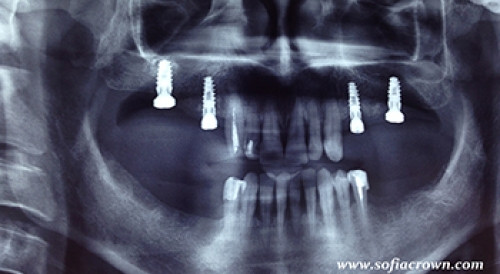

Поставени четири зъбни импланта в горната челюст. Едновременно с това се извърши и повдигане пода на двата максиларни синуса. Метод – закрит синус лифт.